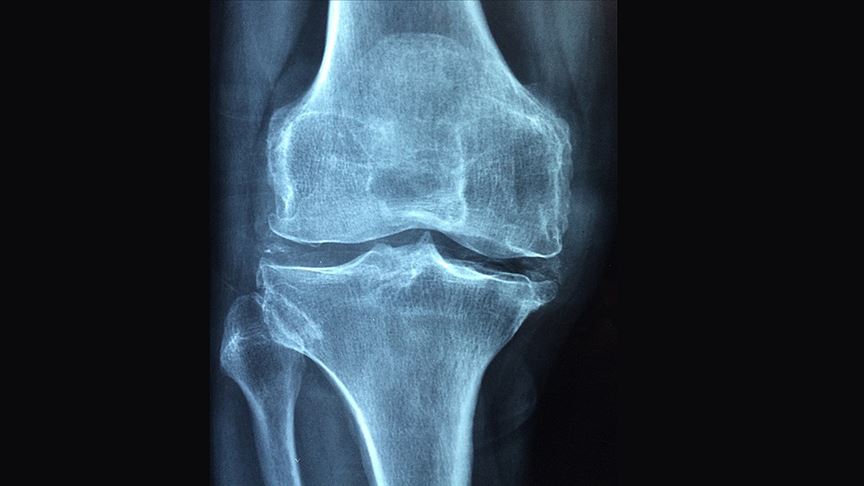

Çok kırıklı ve küçük parçalı kemikler için de aynı zorluk geçerli. Kanlı ve ıslak yara dokusunda kemiklerin yeniden kaynamasını sağlamak ortopedinin en zor alanlarından biri.

İlk deneylere göre ise Bone-02, kemik kırıklarının bulunduğu bölgeye doğrudan enjekte edilebiliyor ve 2-3 dakika içinde kemik parçalarını sabitleyebiliyor. Üstelik kanla dolu ortamlarda bile etkili olabiliyor; bu özellik, şimdiye dek çoğu yapıştırıcının başarısız olduğu bir durum.

Deneye katılan kişilerden biri, travma nedeniyle bileğinde parçalı bir distal radius kırığı olan genç bir işçiydi. Geleneksel tedavi, ameliyatla plaka ve vidaları yerleştirmek için büyük bir kesinin açılmasını gerektiriyordu. Bu, oldukça invaziv (müdahaleci) bir işlem; tendon yapışıklıkları ve sinir hasarı riski taşımakla kalmıyor, aynı zamanda ikinci bir ameliyat gerektiriyordu. Bone 02 deneyinde ekip, sadece 2-3 cm’lik bir kesi açarak yapıştırıcıyı enjekte etti. Üniversite, parçalanmış kemik parçalarının sadece üç dakikada hassas bir şekilde bağlanmasını ve sabitlenmesini sağladıklarını belirtiyor. Üç aylık takip, hastanın kırığının komplikasyonsuz bir şekilde iyileştiğini ve bilek fonksiyonunun tamamen geri kazanıldığını göstermiş.

Özellikle karmaşık kırıklarda, plak ve vidalarla kemiklerin yeniden “inşa edilmesi” yerine, doğal yapıştırıcıyla sabitlenerek iyileşmesi mümkün olabilecek.